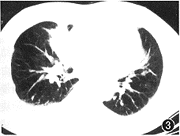

图3 肺窗:右肺中叶内侧段见不规则条片状高密度灶,边缘模糊,CT值47 HU

, http://www.100md.com

图4 为图3纵隔窗:于右中叶片状影内见空气支气管征,并见局限性胸膜病变。术前诊断:右中叶炎症;术后病理诊断:干酪增殖性肺结核

2.呈肺段和肺叶阴影:19例(图3,4),其中11例在病理上表现为支气管内膜结核,在CT上肺段、肺叶影像内见空气支气管征8例,支气管狭窄和梗阻11例,狭窄支气管壁增厚程度不同,多为轻度增厚。CT表现为肺段、肺叶阴影的,在病理上肺段、肺叶内见多发增殖和干酪病灶,这些病灶之间为慢性非特异性炎症。对切除的肺段、肺叶进行CT扫描,有多数病灶的肺段、肺叶的密度均匀,分辨不出肺段和肺叶内病灶的密度差。